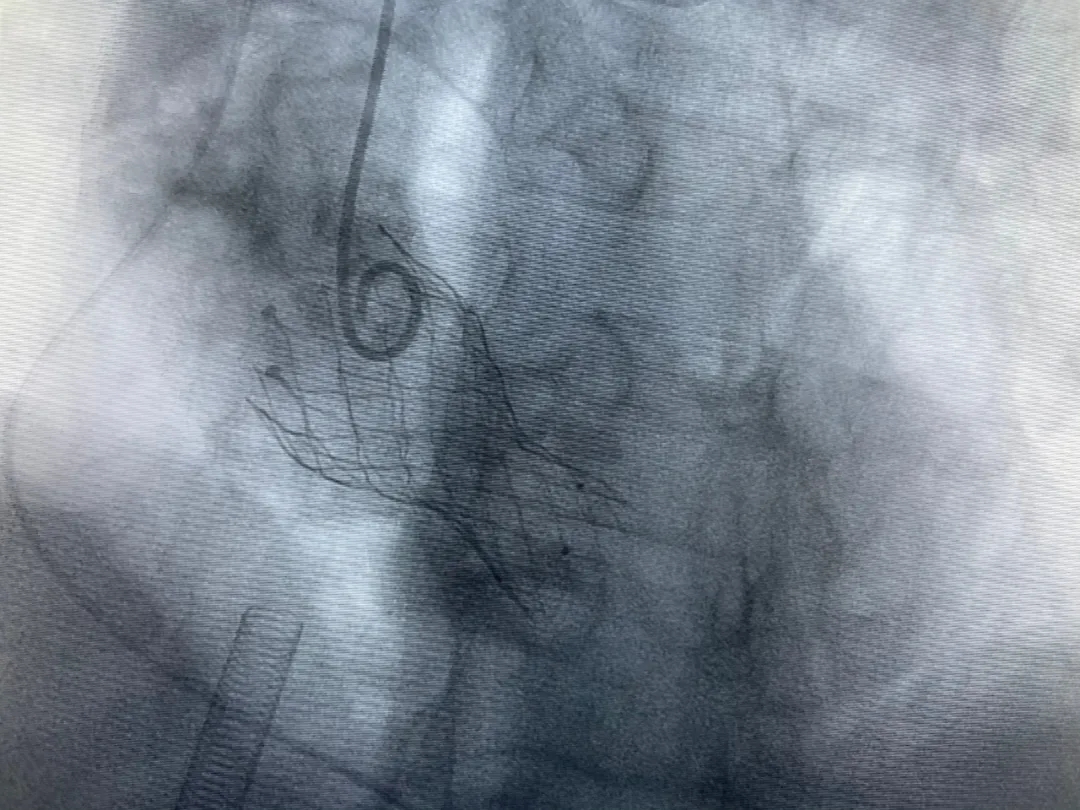

結(jié)合老人病情特點:年齡高、室壁厚、左室腔小、瓣膜鈣化嚴重,術(shù)中球囊擴張和瓣膜釋放過程有循環(huán)崩潰可能;為降低此種風險、最大程度提高手術(shù)成功率,張金洲副院長在術(shù)前組織了由楊金保博士帶領(lǐng)的TAVR團隊多次反復溝通、討論,制定了各種應急處理方案。最終經(jīng)過TAVR團隊的默契配合,手術(shù)歷時2小時,用20#球囊預擴張后順利植入23#主動脈瓣生物瓣膜,再次后擴后主動脈根部造影顯示:人工主動脈瓣生物瓣位置良好,瓣葉開閉正常;冠脈顯影良好。經(jīng)食道超聲顯示:主動脈瓣葉活動度良好,主動脈跨瓣壓差約35mmHg,未見瓣周漏及明顯返流。出手術(shù)室前老人便已蘇醒,自訴憋悶癥狀完全消失。